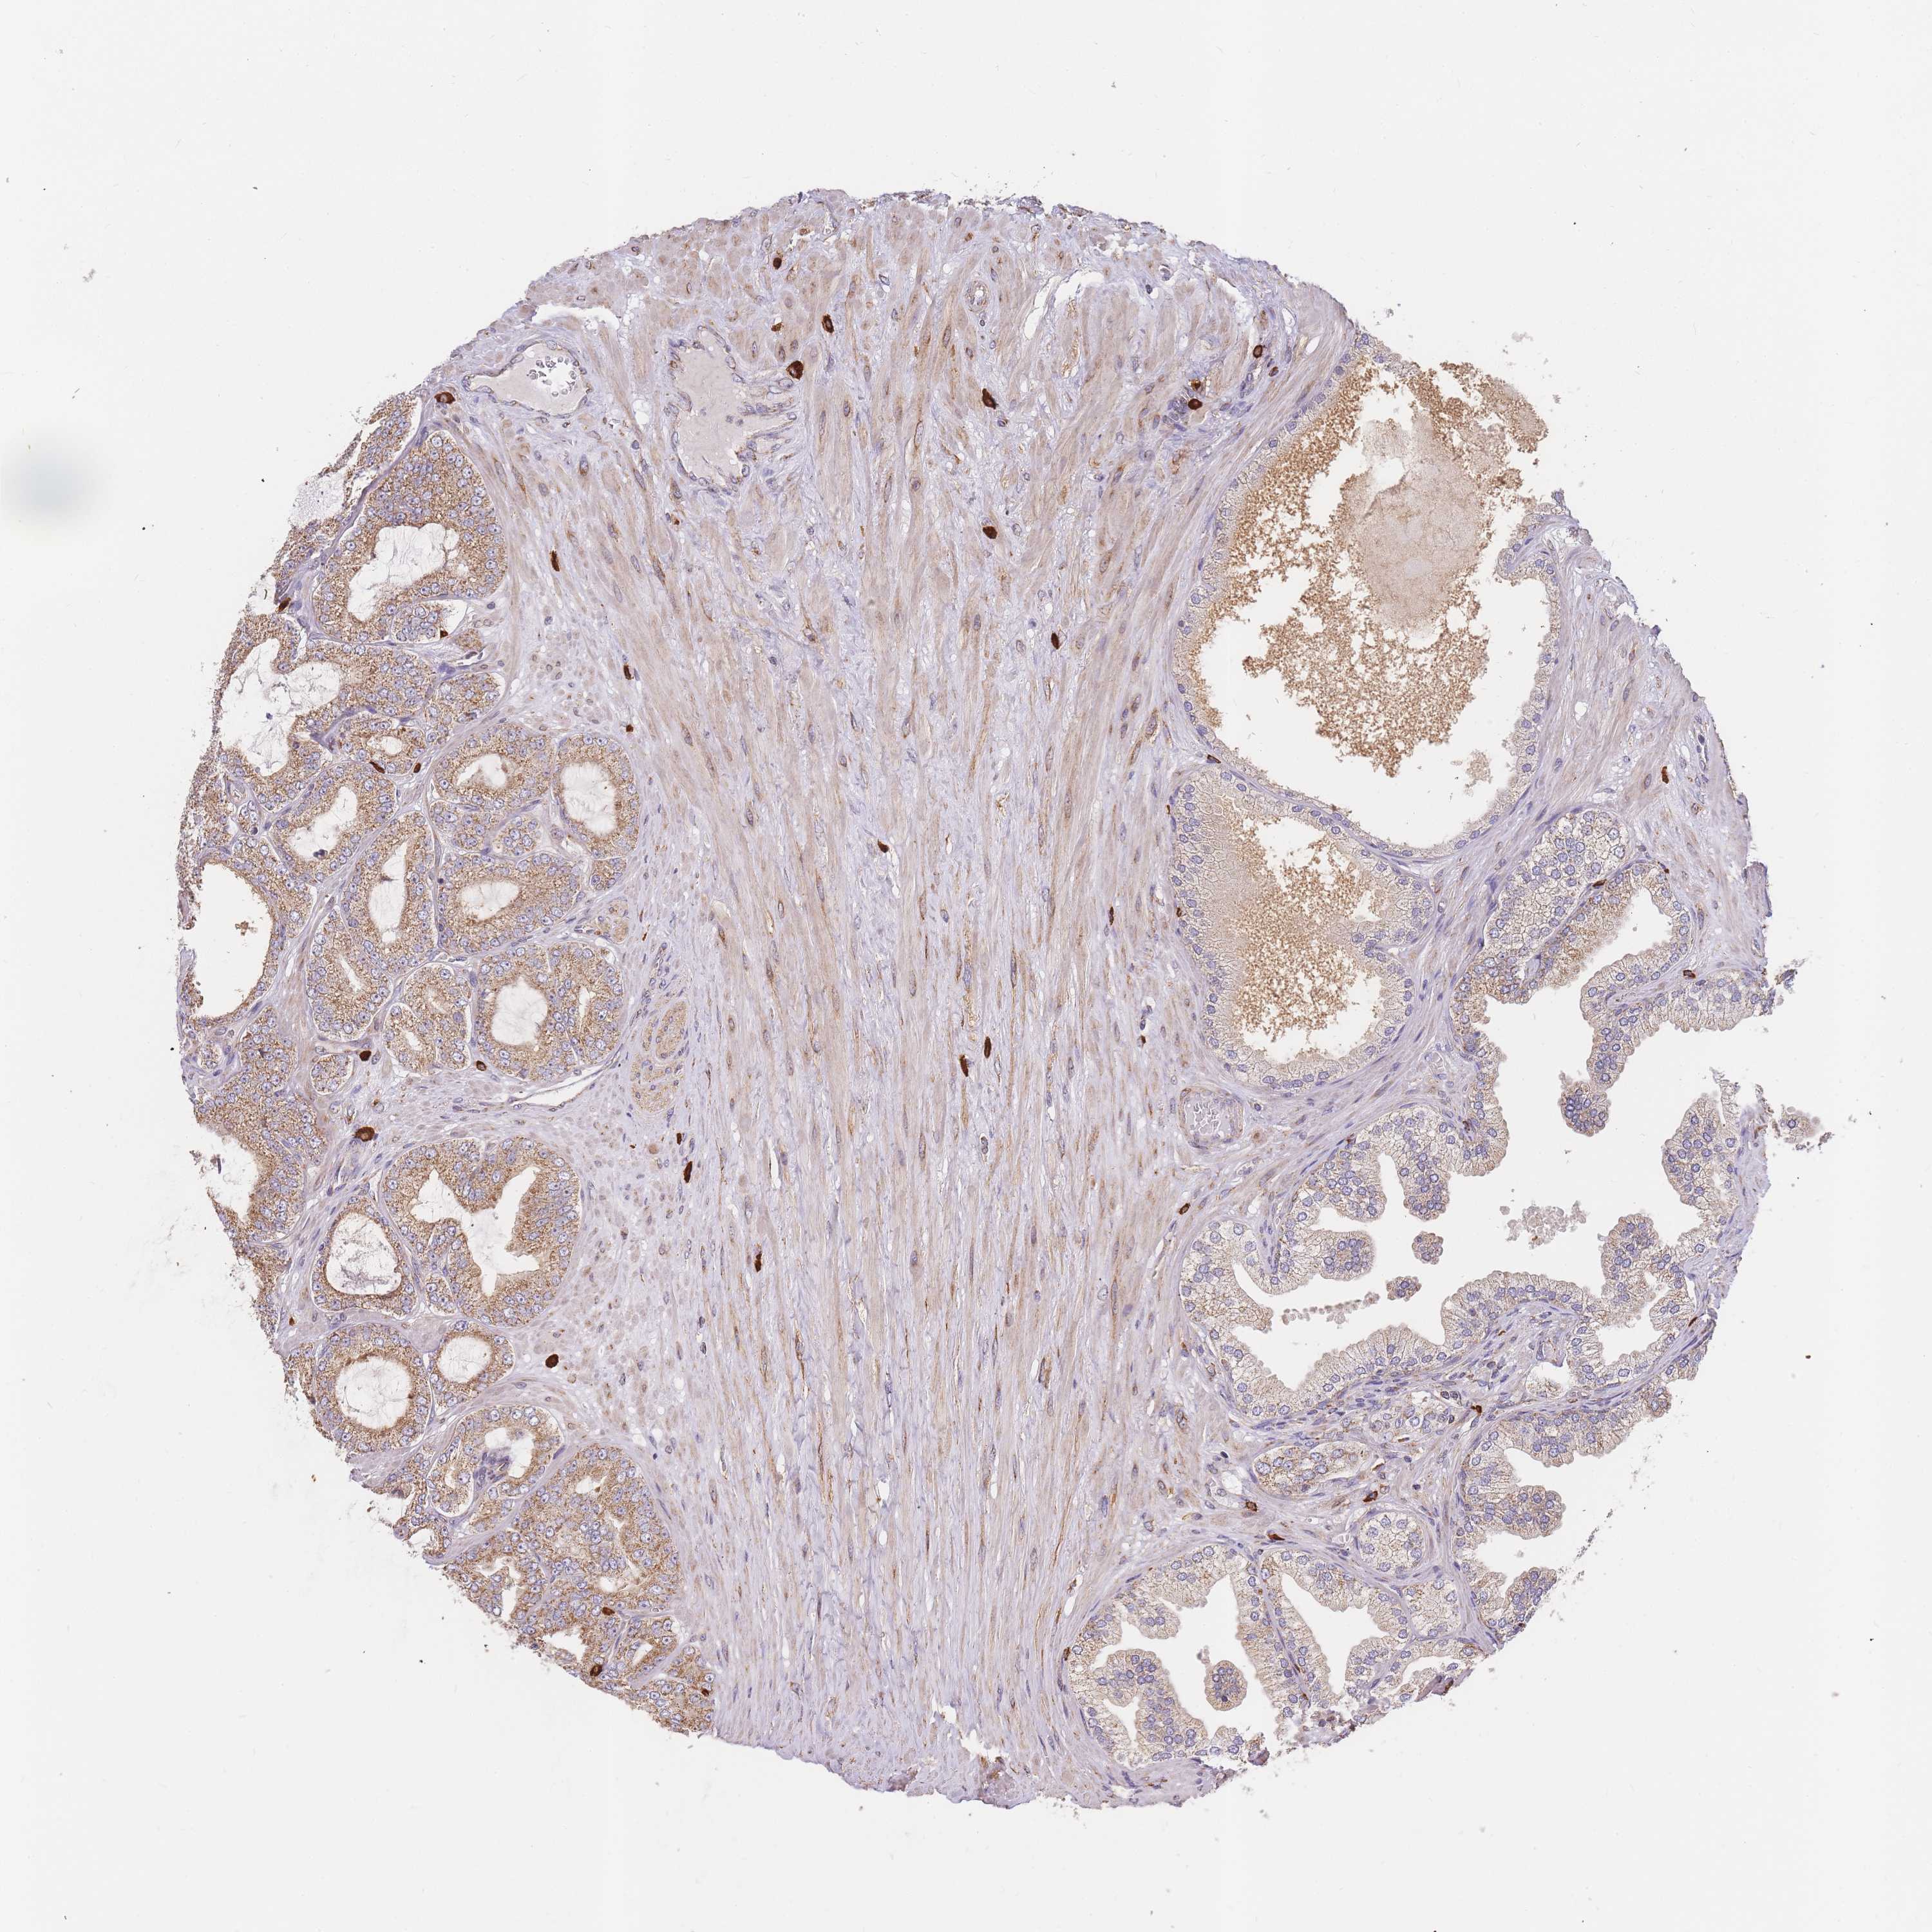

PROSTATE CANCER - Protein expressioni

A mouse-over function shows sample information and annotation data. Click on an image to view it in a full screen mode. Samples can be filtered based on level of antibody staining by selecting one or several of the following categories: high, medium, low and not detected. The assay and annotation is described here.

Note that samples used for immunohistochemistry by the Human Protein Atlas do not correspond to samples in the TCGA dataset.

Antibody stainingi

Antibody staining in the annotated cell types in the current human tissue is reported as not detected, low, medium, or high, based on conventional immunohistochemistry profiling in selected tissues. This score is based on the combination of the staining intensity and fraction of stained cells.

Each image is clickable and will lead to virtual microscopy that enables deeper exploration of all samples and also displays staining intensity scores, fraction scores and subcellular localization as well as patient and tissue information for each sample.

Antibody HPA041328

Antibody HPA044225

Staining

High

Medium

Low

Not detected

Intensity

Strong

Moderate

Weak

Negative

Quantity

>75%

75%-25%

<25%

None

Location

Nuclear

Cytoplasmic/membranous

Cytoplasmic/membranous,nuclear

Adenocarcinoma, NOS

Adenocarcinoma, High grade

Adenocarcinoma, Low grade